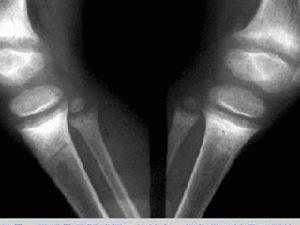

人體組織結構,是由不同元素所組成,依各種組織單位體積內各元素量總和的大小而有不同的密度。人體組織結構的密度可歸納為三類:屬於高密度的有骨組織和鈣化灶等;中等密度的有軟骨、肌肉、神經、實質器官、結締組織以及體內液體等;低密度的有脂肪組織以及存在於呼吸道、胃腸道、鼻竇和乳突內的氣體等。

檢查儀器骨關節的X線檢查主要用攝片,不用透視。只在火器傷尋找異物與定位時和在外傷性骨折與脫位進行復位時採用。

攝影要注意以下幾點:①任何部位,包括四肢長骨、關節和脊柱都要用正、側兩個攝影位置。某些部位還要用斜位、切線位和軸位等;②應當包括周圍的軟組織。四肢長骨攝片都要包括鄰近的一個關節。在行脊柱攝影時,例如攝照腰椎應包括下部胸椎,以便計數;③兩側對稱的骨關節,病變在一側而症狀與體徵較輕,或X線片上一側有改變,但不夠明顯時,應在同一技術條件下攝照對側,以便對照。